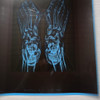

Хочу написать отзыв о враче Чернышове Н. А. который является так же директором центра как и «хирургом»..... 5.11.2025 была прооперирована (Удаление вальгусной диформации) мама у этого доктора если так можно назвать. Вроде бы все нормально поначалу как казалось, 21.11 2025 сняли швы и тут доктор начал говорить намёками что операции приходится повторять и тд… 26. 11.25 вынал спицы врач Пасечник, после этого пальцы второй третий стали кривыми как изначально и боль была в течении 3х дней. 22.12.25 с новыми снимками приехали к врачу с новыми снимками, я выразила свое недовольство что если на правой ноге более менее результат есть то на левой его нет совсем, на левой ноге не заживает глубокая рана, нога опухшая, на что он сказал нужно переоперироваться, опять оплатить якобы за расходные материалы....А так все нормально у вас. На что я сказала почему мы должны платить если с первого раза вы результат не сделали… Ответа не было… Шли дни из ноги началась выделяться жидкость, затем гной, 30.12.25 около 21 часа я наконец то дозвонилась Чернышове Н. А. отправила фото ноги с гноем, он сказал срочно ехать в Семилуки в больницу ложится, так как НМЦ закрыт на праздники… В суете и переживаниях собрались поехали в метель в Семилуки, хотя странно почему в Семилуки, потом понятно стало там зав. отделения Чернышов М. А???? Не право ли совпадение… Маму положили, назначили антибиотики, сожгли ногу Бетодином ежедневно уливая им её. Взяли анализы, это тоже история превышен белок у неё, а ей об этом никто ни слово и не обследовали… Выписали, поехали мы в НМЦ к ЧЕРНЫШОВУ Н. А. Он обработал хлоргексидином и все, нога опухшая, рана открыта, на вопрос может кроме хрлгексидина нужно купить что то ещё он со злостью ответил не надо тут самолечением заниматься. А нужно было почистить рану вынуть белое скопление которое не давало стягиваться и заживает, не говоря о том что отломок кости после операции остался не тронутым!!! По анализам перед операцией был восполительный процесс, оперировать нельзя было, но как же день назначен терять центру 261000 не хотелось бы.... Итог на данный момент мама ходит в спец. обуви, рана ещё не затянулась, из дома естественно она не выходит 4 месяца как. Врач после всего естественно общается с недовольством, пишите притензию в юр. отдел наш написал в личные сообщение… Рассказала вам нашу историю, надеюсь может кому то поможет что надо обходить этот центр и этого хирурга далёкой стороной, хотя на сайтах одни положительные отзывы, которому важно только заработок, а не здоровье и восстановление пациента.